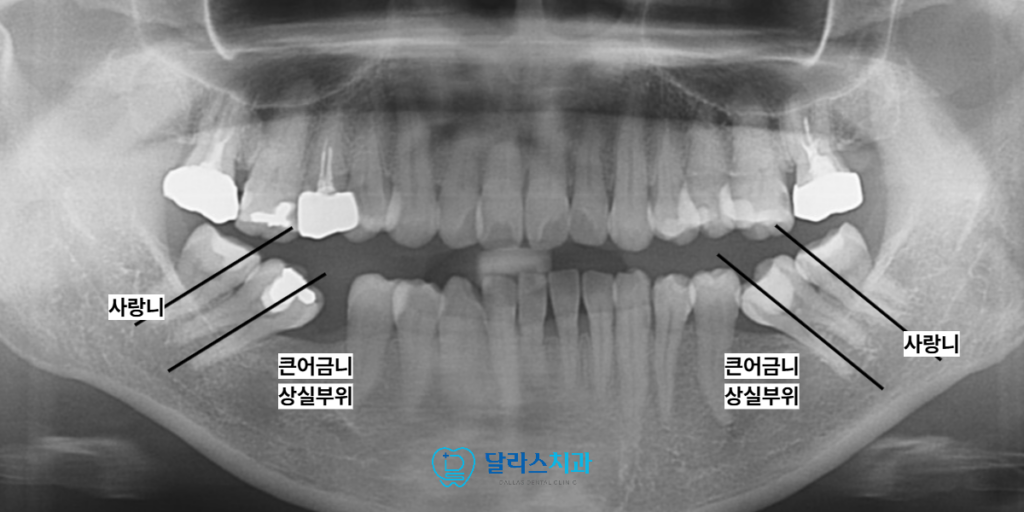

노원치과 환자분께서는 아래 양쪽의 첫 번째 큰어금니 치아를 상실하신 이후

상당한 시간이 흐른 상태에서 내원하셨습니다.

정밀 검사 결과 상실된 부위 뒤편에 위치한

두 번째 큰 어금니 치아들이 앞쪽으로 심하게 기울어져 있었으며

위쪽 어금니들은 지지대를 잃고 아래로 많이 내려와

전체적인 교합 평면이 심하게 어긋나 있었습니다.